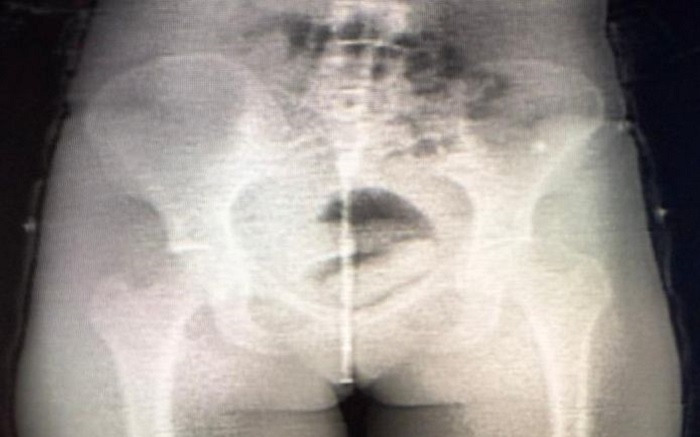

A ocorrência foi detectada por meio do equipamento Body Scan, utilizado no controle de acesso durante o horário de visitação. Por volta das 11h, durante inspeção na Galeria A, o equipamento apontou anormalidade, indicando indícios de possível ocultação interna de material ilícito.

Diante da fundada suspeita, a visitante foi encaminhada ao Hospital Regional de Irecê para realização de exame de imagem complementar (tomografia computadorizada), que confirmou a presença de corpo estranho em cavidade corporal.